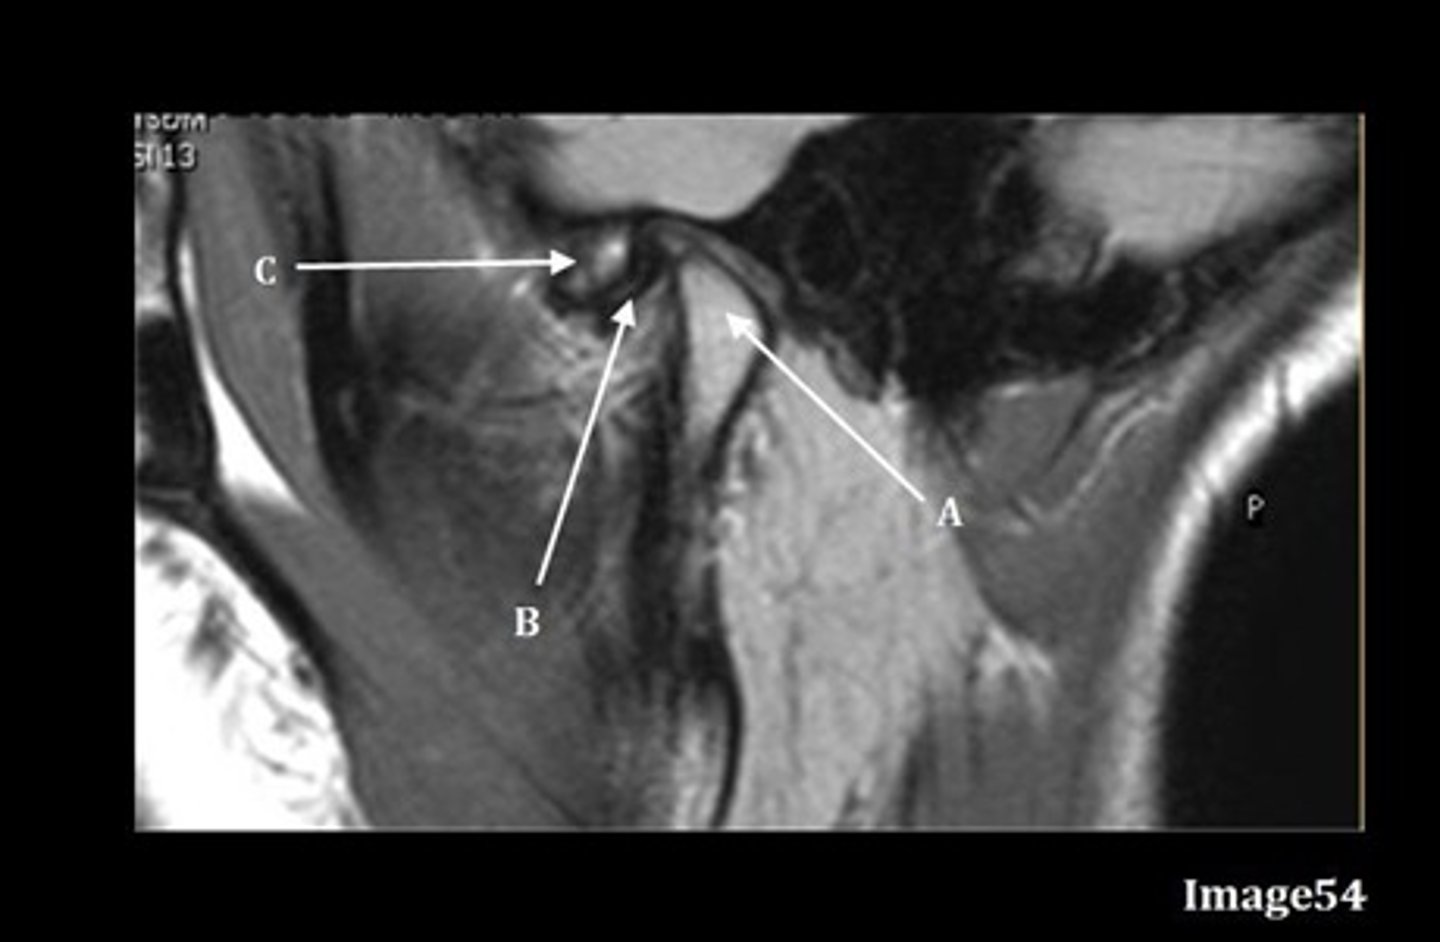

A- mandibular condyle inside mandibular fossa of temporal bone

B- articular disc

C-articular tubercle